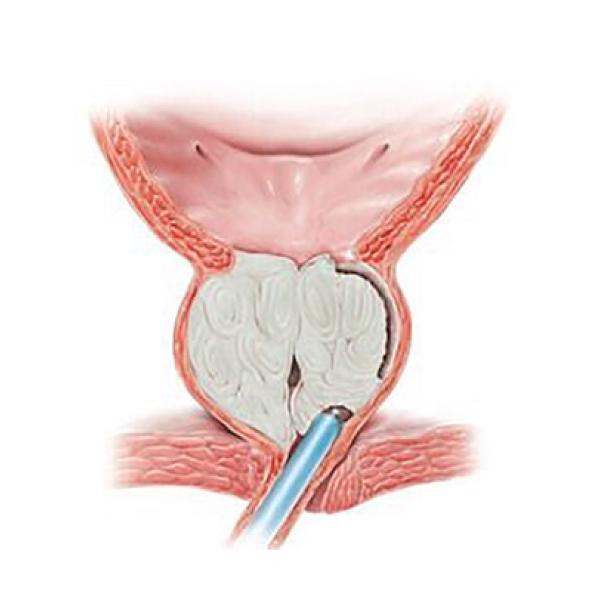

Посетив уролога по поводу увеличения в объеме яичка и его твердости сделал узи с доплерографией, сдал кровь на маркеры, сделал биопсию (с 2-х разных частей яичка). Была назначена повторная биопсия (сделана с 3-х разных частей). Естественно после такого количества манипуляций возникает настороженность. Биопсия хорошая, маркеры в норме. Диагноз так и не поставлен! Можно ли по этим анализам говорить что имеет место просто орхит?

Посетив уролога по поводу увеличения в объеме яичка и его твердости сделал узи с доплерографией, сдал кровь на маркеры, сделал биопсию (с 2-х разных частей яичка). Была назначена повторная биопсия (сделана с 3-х разных частей). Естественно после такого количества манипуляций возникает настороженность. Биопсия хорошая, маркеры в норме. Диагноз так и не поставлен! Можно ли по этим анализам говорить что имеет место просто орхит?

По представленным результатам убедительных данных за наличие онкологического процесса в правом яичке нет. Однако для точной постановки диагноза важна клиническая картина и этапы развития заболевания. Сопутствовало ли увеличению яичка повышение температуры тела или выделения из уретры, как быстро развилось увеличение яичка и т.д. Об этом Вы ничего не сообщаете. Также важно исключить специфических возбудителей и ЗППП. Кроме того, важно оценить эффективность назначенного противовоспалительного и антибактериального лечения - и назначали ли его?

По представленным результатам убедительных данных за наличие онкологического процесса в правом яичке нет. Однако для точной постановки диагноза важна клиническая картина и этапы развития заболевания. Сопутствовало ли увеличению яичка повышение температуры тела или выделения из уретры, как быстро развилось увеличение яичка и т.д. Об этом Вы ничего не сообщаете. Также важно исключить специфических возбудителей и ЗППП. Кроме того, важно оценить эффективность назначенного противовоспалительного и антибактериального лечения - и назначали ли его?